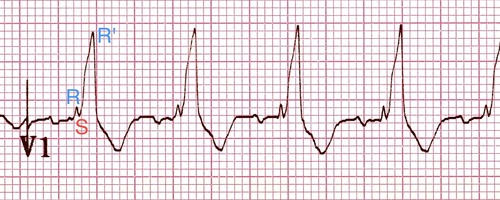

Bundle Branch Block